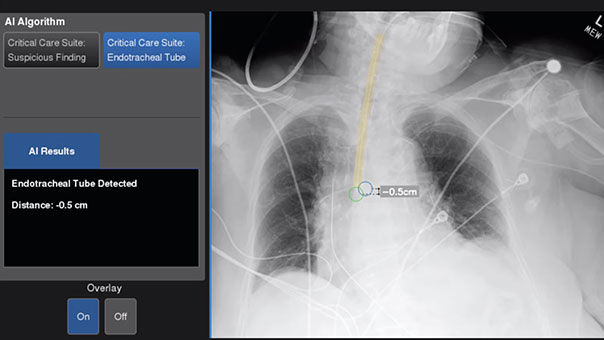

Definium™ 656 HD Upgrades

Helix™ Automated AI Brightness and Contrast automatically adjusts brightness and contrast to a user-defined preference and can help reduce technologist image processing time by up to 87%.⁴